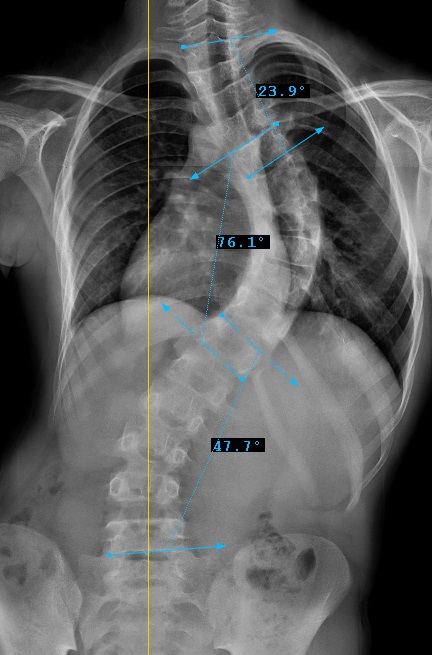

Preop: 1A+ Samples

Preop LAT View